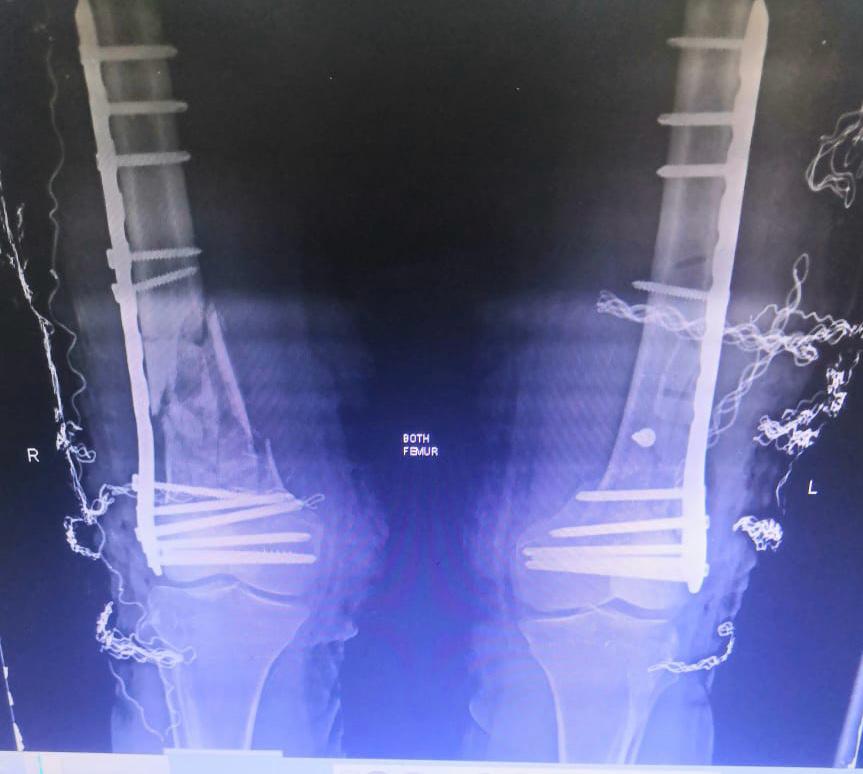

Trauma surgeries focus on the management of complex injuries resulting from accidents, falls, or high-impact trauma. Prompt surgical intervention is provided to stabilize injuries, promote proper healing, and restore function while minimizing long-term complications.

We provide surgical management for fractures involving the upper and lower limbs, including arms, forearms, thighs, legs, and ankles. Treatment aims to achieve proper bone alignment, stable fixation, and optimal functional recovery through modern orthopedic techniques.